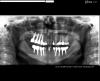

Marusya_new Опубликовано 7 октября, 2012 Поделиться Опубликовано 7 октября, 2012 (изменено) Добрый день.Почти полгода жую зубами на имплантах.Очень хочется получить прогноз на их дальнейшее присутствие у меня во рту .В хронологическом порядке: синуслифтинг (верх справа), операция (12 имплантов), начало мая окончание протезирования (верхние части зубов на винтах, кроме 4 верха справа).Проблема: с недавнего времени неприятные очущения во время обработки ирригатором над 7 сверху справа и между 5 и 6 слева снизу. Немножко больно. Т.к. снимок по окончании имплантации не делала (врач почему-то решил, что этого делать не надо), сделала его сейчас.Своим взглядом неспециалиста... Верх справа: 6 и 7 - в гайморовой полости (7, по-моему, лишний), 4 - упирается в корень 3. Низ: 4 справа и 4 слева - упираются в корни 3-ек. Верх протезов почти всех зубов неплотно прикручен к имплантам.Пожалуйста, помогите разобраться, что и где правильно и неправильно. Изменено 7 октября, 2012 пользователем Marusya_new Ссылка на комментарий

Bier Опубликовано 7 октября, 2012 Поделиться Опубликовано 7 октября, 2012 нахождение имплантата в пазухе не является проблемой.говорить по плоскостному снимку упирается имплантат в корень или нет - нельзя.Абатменты и коронки на абатментах посажены до конца, все прикручено плотно. Патологических изменений на снимке не видно. Ссылка на комментарий